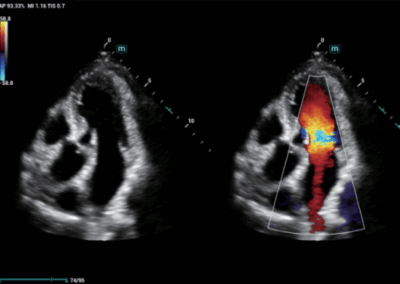

Nuewa i8

El Nuewa I8, ofrece una claridad de imagen inigualable, elevando tu confianza y eficiencia a nuevas alturas. Diseñado con el máximo cuidado, minimiza la fatiga y maximiza la conveniencia a lo largo del proceso de operación.

Impulsado por la innovadora plataforma ZST + y un conjunto completo de soluciones inteligentes, el Nuewa I8 ofrece una claridad de imagen inigualable, impulsando tu confianza y eficiencia a nuevas cotas. Diseñado con la máxima atención al detalle, minimiza la fatiga y maximiza la comodidad durante todo el proceso quirúrgico.